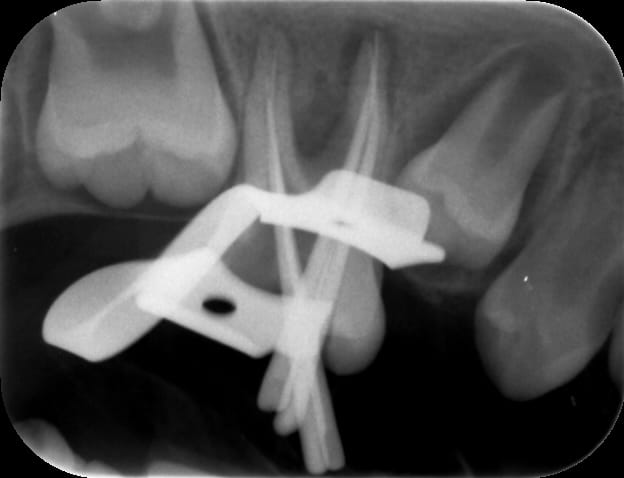

Je fais donc le parage: sous digue, avec hypochlorite , système de préparation Hero Shaper, radio cône calibré en place ok.

Voici des radios:

Per op qyau2v - Eugenol